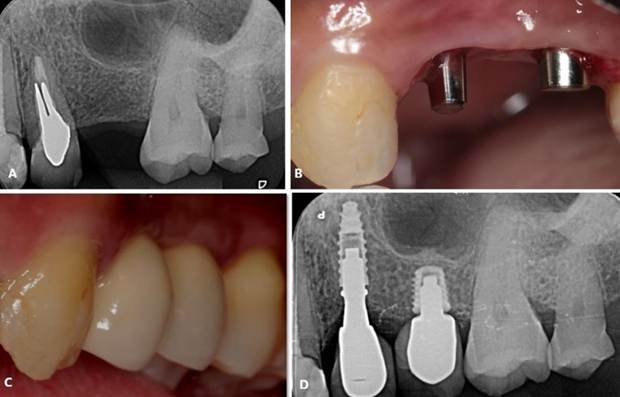

Paciente R. G, sexo feminino, 49 anos de idade, compareceu ao consultório particular para reabilitação da região edêntula. O paciente relatou ausência de histórico de alterações sistêmicas e de alergias. Ao exame clínico e radiográfico, evidenciado ausência do elemento dentário 24 e pouca altura óssea no 25 (Figura 18. A). O tratamento consistiu pela exodontia do 25, seguida pela instalação de implante ARCSYS (FGM, Joinvile – SC, Brasil) 3,3 mm x 11,0 mm na região do 24, e implante curto 4,3 mm x 5,0 mmcurtos ARCSYS (FGM, Joinvile – SC, Brasil) no 25, e posterior reabilitação protética (Figura 18. B, C). O acompanhamento clínico e radiográfico evidencia resultado estável e satisfatório (Figura 18. D).

Figura 18. A) Radiografia periapical inicial. B) Condição clínica após a realização dos implantes. C) Reabilitação protética. D) Radiografia periapical final.